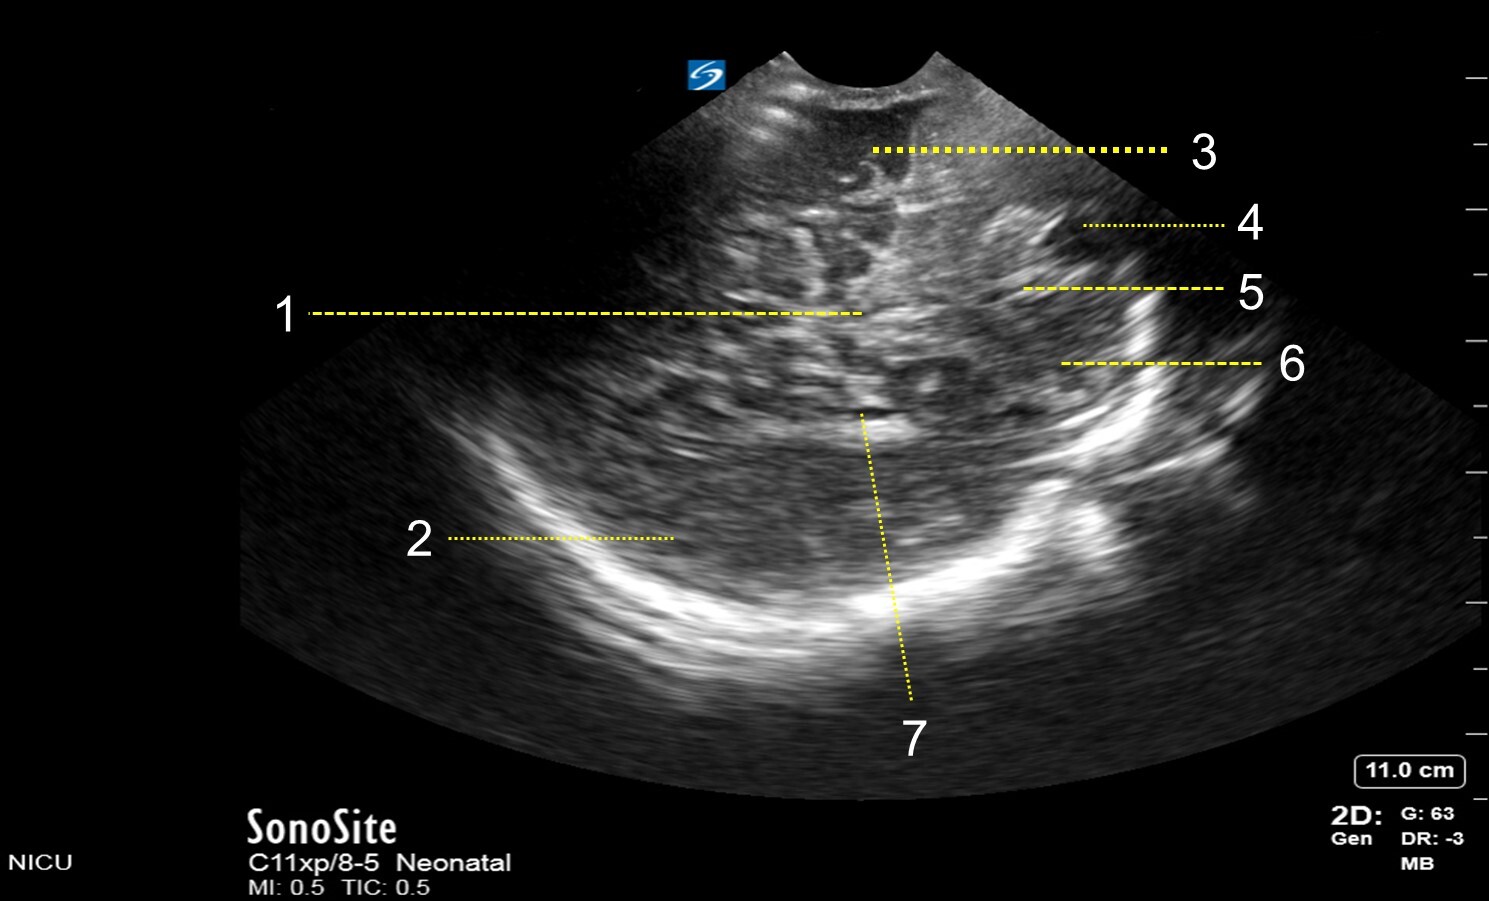

Neonatology Mastoid Fontanel – Anterior Coronal View Image

1. Cerebellar Vermis

2. Parietal Lobe

3. Temporal Lobe

4. Cisterna Magna

5. Foramen of Magendie

6. Cerebellar Hemisphere

7. Temporal Horn of Lateral Ventricle